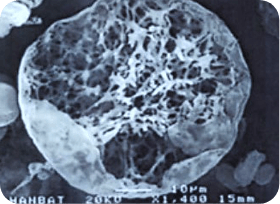

< 다공성 원형구조 미세분자 >

쥬베룩의 입자 형태

크기가 굉장히 작고 둥글기 때문에

결절이 잘 생기지 않고

생분해성으로 체외로 모두 배출되기 때문에

체내에 잔존물이 거의 남지 않습니다.

둥글게 생긴 다공성 망상구조의 입자가

콜라겐 재생효과를 비교적 오래 유지